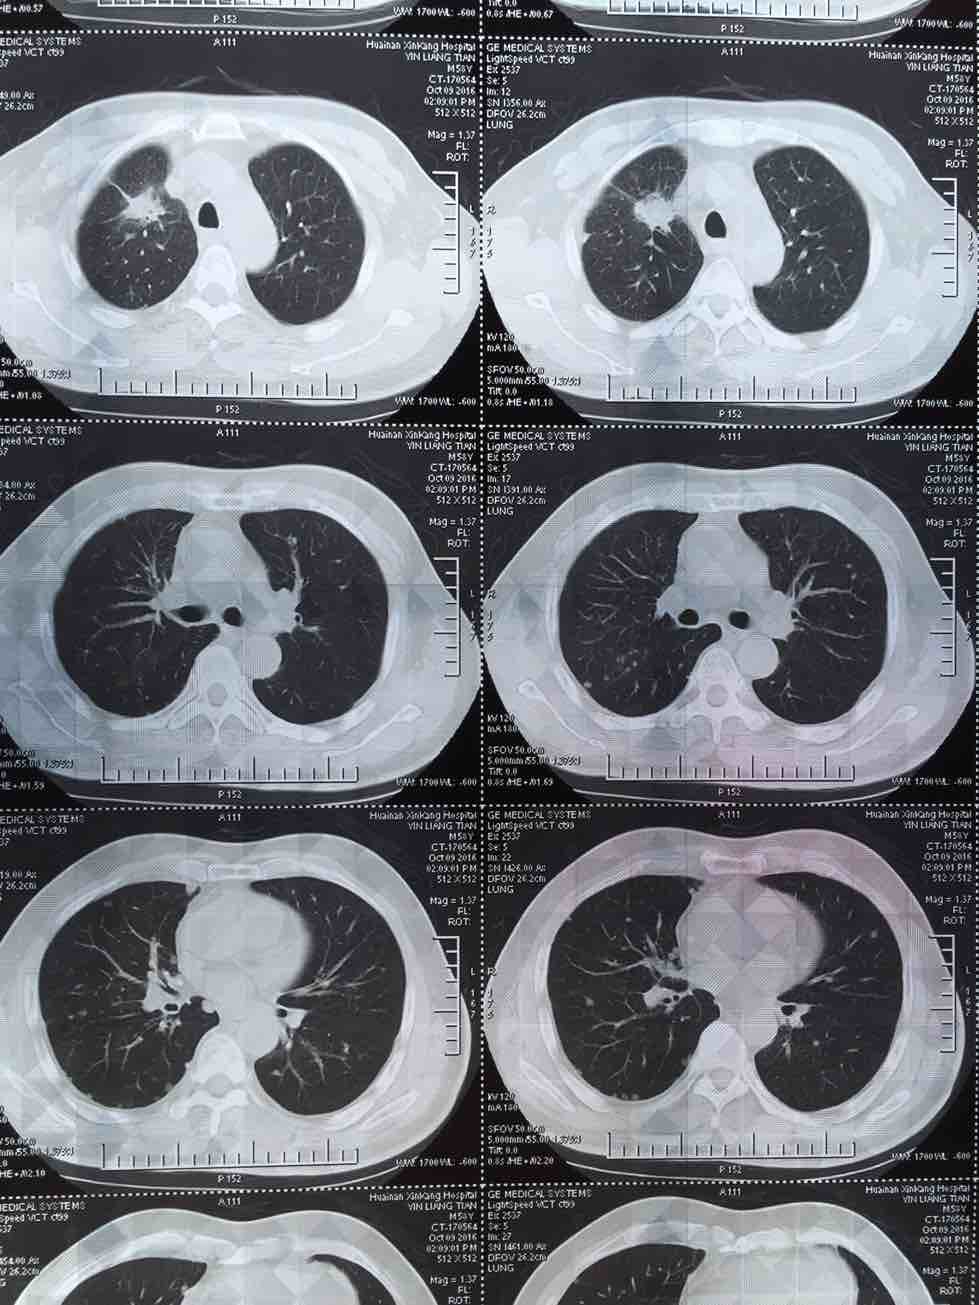

肺腺癌晚期治疗经验

我父亲今年一月份查出肺腺癌晚期伴两肺及腰椎骨盆转移,吉西他滨 顺铂两次,无效,后培美曲塞用了六次,最后一次今年7月25号出院,控制很好,期间主病兆放疗15次有所缩小,今年10月15号复查,两肺转移兆增多增大,紧接着做穿刺基因检测,结果野生型,顿时绝望,盲吃易瑞莎一个月,老天爷眷顾有效,病兆明显缩小或消失!!